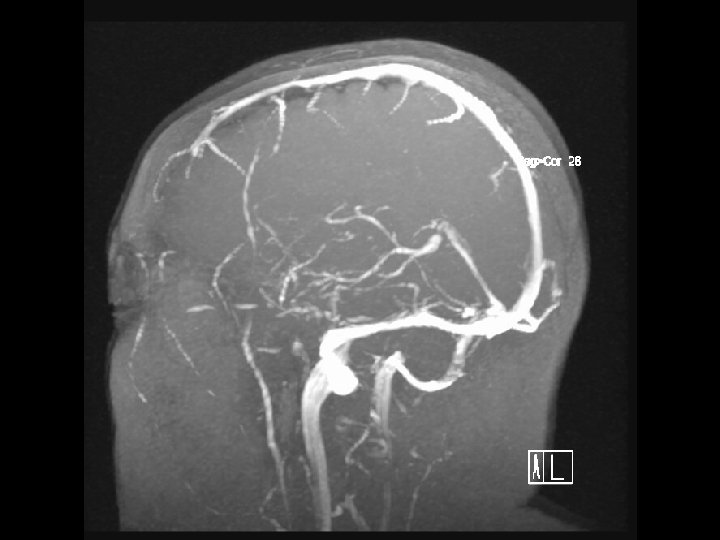

Arterial Blood Supply

Anterior circulation Internal carotid arteries Posterior circulation Vertebral arteries